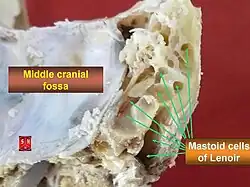

The mastoid cells (also called air cells of Lenoir or mastoid cells of Lenoir) are air-filled cavities within the mastoid process of the temporal bone of the cranium. The mastoid cells are a form of skeletal pneumaticity. Infection in these cells is called mastoiditis.

Extent

They may excavate the mastoid process to its tip, and be separated from the posterior cranial fossa and sigmoid sinus by a mere slip of bone or not at all. They may extend into the squamous part of temporal bone, petrous part of the temporal bone zygomatic process of temporal bone, and - rarely - the jugular process of occipital bone; they may thus come to adjoin many important structures (including the bony labyrinth, tympanic cavity, external acoustic meatus, pharyngotympanic tube, superior jugular bulb, posterior cranial fossa, middle cranial fossa, carotid canal, abducens nerve, sigmoid sinus) to which they may disseminate infection in case of infective mastoiditis.[1]: 746

Infections in the middle ear easily spread into the mastoid air cells through the aditus ad antrum, resulting in mastoiditis, a potentially dangerous and life-threatening condition. Infection may then further spread into the middle cranial fossa or posterior cranial fossa, causing meningitis or abscess of adjacent brain tissue. Infection may also spread to muscles of the neck, causing pain and torticollis.[1]: 746